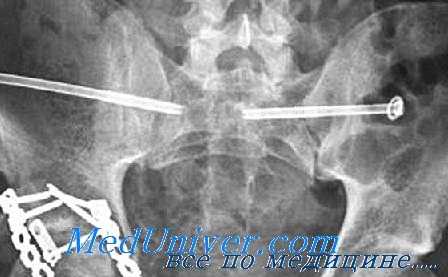

(Слева) КТ у мужчины 19 лет, упавшего с высоты 6 метров и приземлившегося на бок, аксиальный срез. Определяется вколоченный перелом через вторую зону крыла крестца слева, что указывает на травму по типу ла -теральной компрессии. Перелом со смещением правого крестцово-подвздошного сочленения указывает на передне-заднее направление приложения силы по отношению к правой половине таза. Это нестабильный таз, ЛК III.

(Справа) КТ, коронарный срез: у этого же пациента определяется вколоченный перелом крестца слева и полный разрыв крестцово-подвздошного сочленения справа вследствие передне-заднего направления приложения силы. ЛК III встречаются редко. (Слева) При рентгенографии в передне-задней проекции у мужчины 35 лет определяется травма по типу ВТ. Левое крестцово-подвздошное сочленение полностью разорвано, левая половина таза смещена кверху, а также отмечаются переломы лобковой кости справа и подвздошной кости слева. Крестцово-подвздошное сочленение справа расширено спереди.

(Справа) КТ, аксиальный срез: у этот же пациента определяется диффузное расширение левого КПС, указывающее на полный разрыв передних и задних связок левого крестцово-подвздошного сочленения. Правое крестцово-подвздошное сочленение расширено только спереди. (Слева) КТ, 3D реконструкция: у женщины 75 лет определяются переломы по типу ЛК I. Отмечаются косые переломы ветви лобковой кости слева и вколоченный перелом 2 зоны крестца слева.

(Справа) КТ, 3D реконструкция: у мужчины 50 лет определяется травма по типу ПЗК II. Лобковый симфиз расширен >2,5 см. Левое крестцово-подвздошное сочленение расширено спереди, но сзади нормальное. Задние крестцово-подвздошные/ сочленения/связки также должны быть оценены на других проекциях, поскольку при разрыве формируется нестабильная травма по типу ПЗК III.